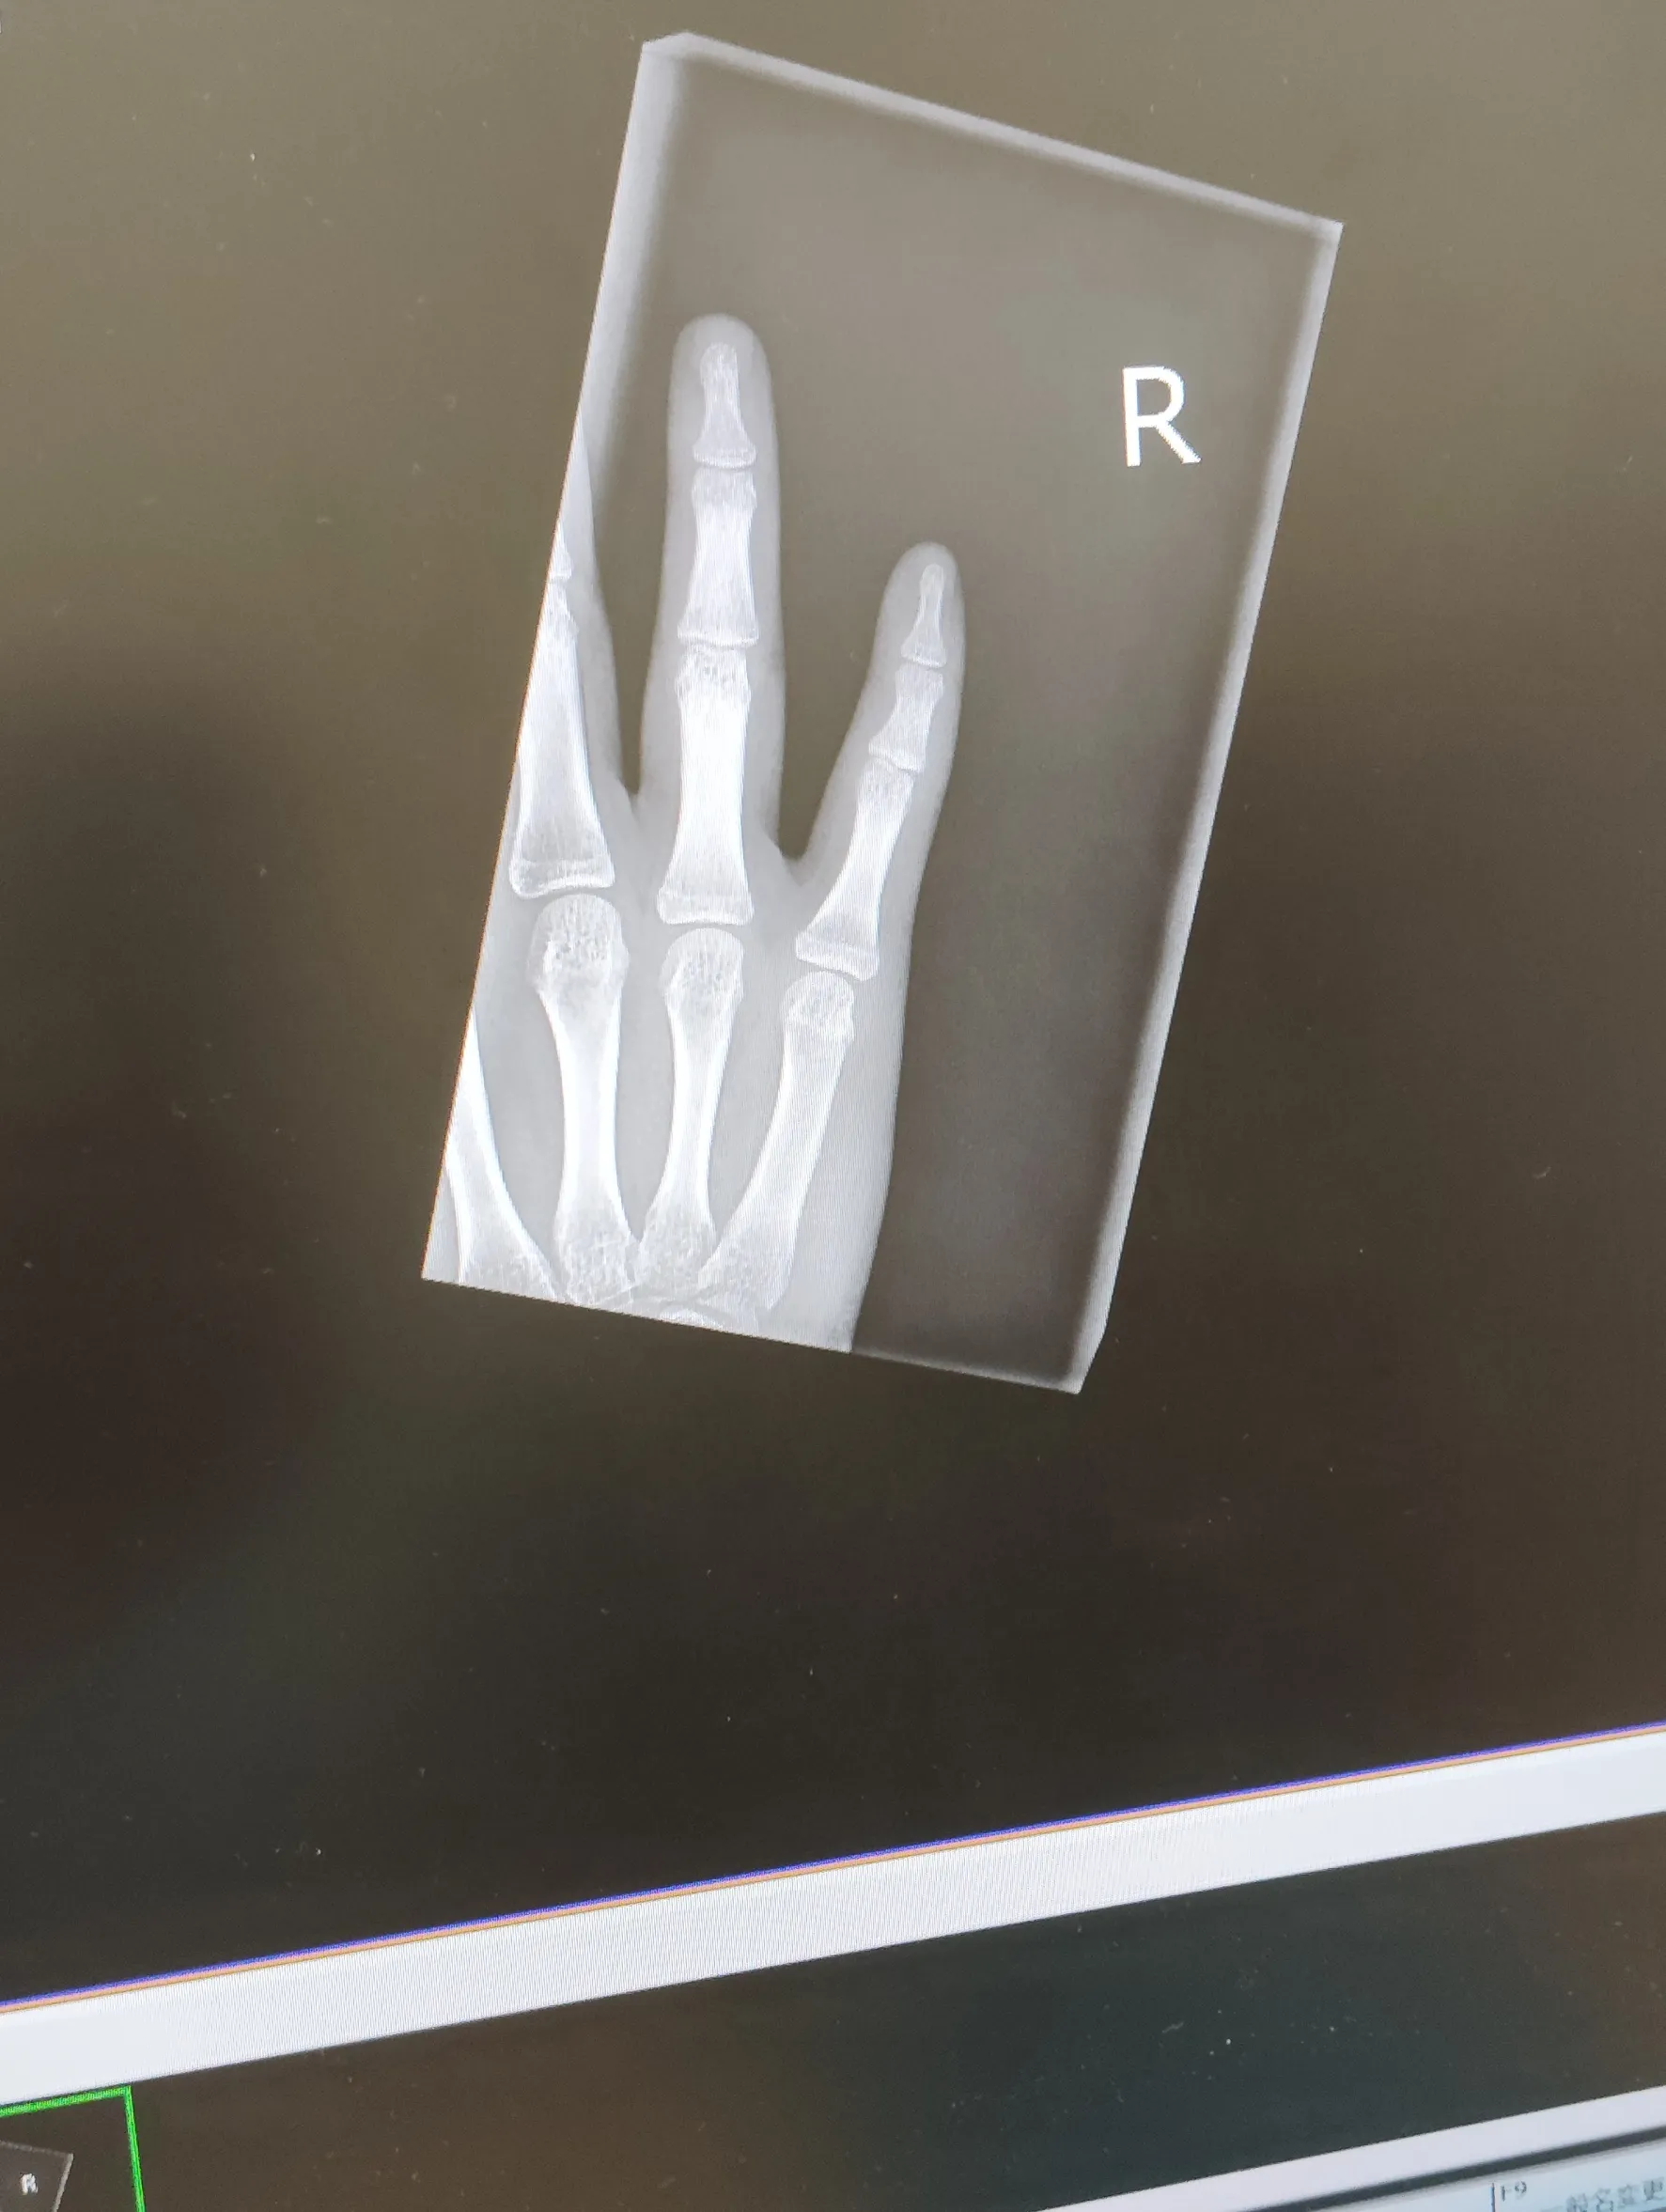

骨折治ってきた

「るあチャン」の投稿画像